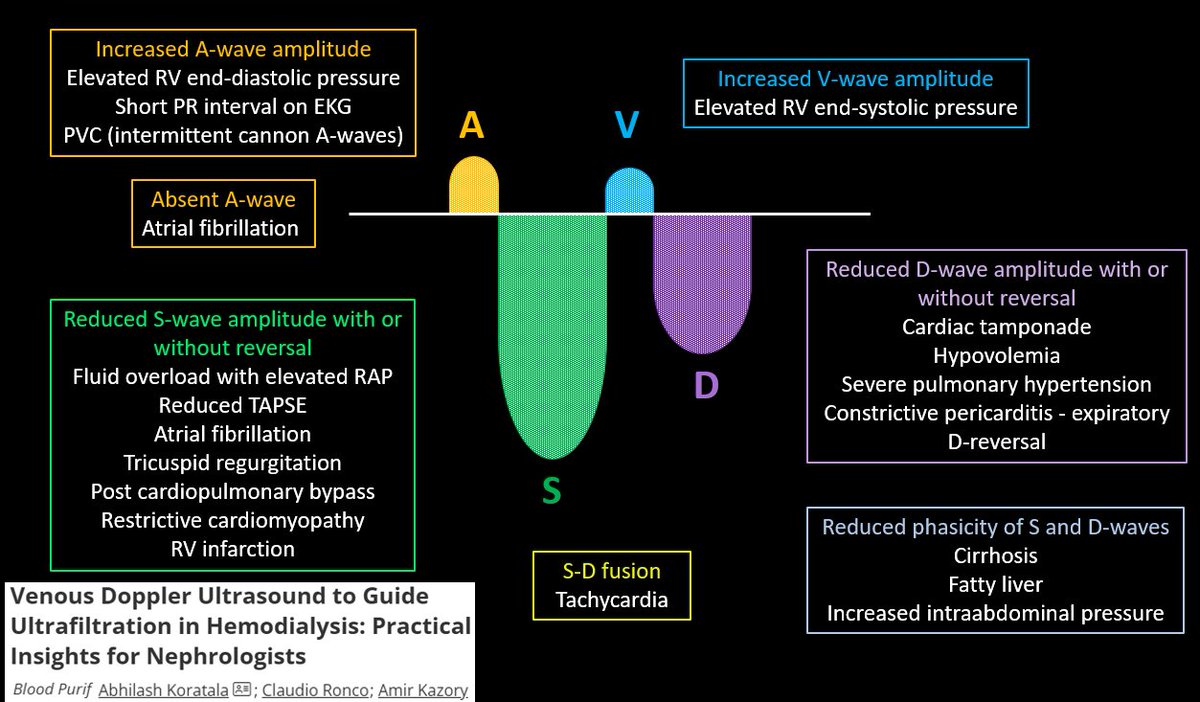

Honored to contribute this invited commentary on #POCUS and #VExUS for guiding ultrafiltration in #dialysis patients, alongside Professors Amir Kazory and Ronco—a cautionary note for clinicians & researchers to avoid key pitfalls. #Nephpearls #MedEd 🔗karger.com/bpu/article-ab…